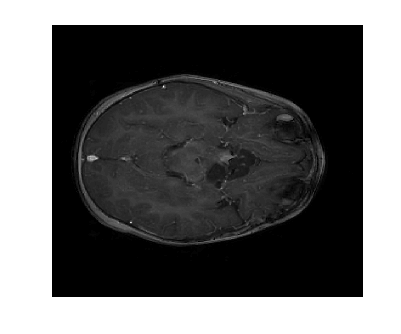

Figure 2: Image reconstruction from Case 20 (a, b, and c) and Case 3 (e, f, and g) of a brain image. Case 20 is the best performing algorithm that uses L1-W and case 3 is the best performing algorithm that uses LACS-MRI

The phantom image that we used in the previous experiment is flat and has less texture while the brain images has a lot of wrinkles and complex shapes. While the phantom image is small, the brain image is too large to calculate fNDsubscript𝑓𝑁𝐷f_{ND} efficiently. Thus, we conducted an experiment in the same setting as the phantom image excluding cases using fAsubscript𝑓𝐴f_{A}: cases 6 through 8 and 14 through 16. In this experiment, contrary to results for the phantom image experiment, L1-W performs better than LACS-MRI. For example, Case 3 performed the best among cases using LACS-MRI but it performs worse than 6 cases that use L1-W. Interestingly, one of the cases that shows an outstanding image recovery purely uses fVDSsubscript𝑓𝑉𝐷𝑆f_{VDS} with L1-W. However, purely using fVDsubscript𝑓𝑉𝐷f_{VD} with L1-W shows a dramatically worse performance. In conclusion, we are unsure why each combination of mixed PDFs and reconstruction algorithm perform differently based on the images processed, but this differing behavior is crucial to highlight for practical applications. We conjecture that the texture of the image is one factor that decides the performance of each algorithm. In the future, we may explore this conjecture and analyze why this happens.